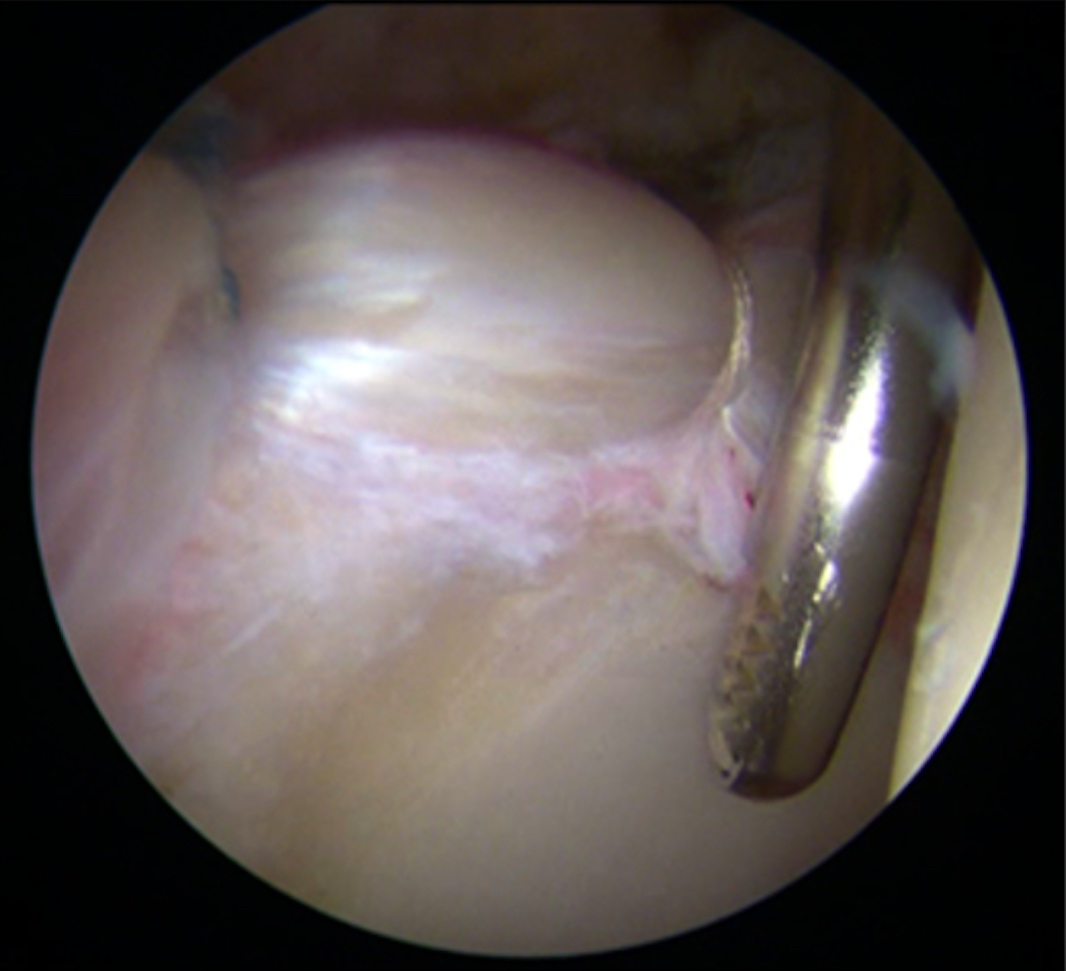

Il conflitto femoro-acetabolare comporta una lesione del labbro acetabolare

(Fig.2), che è una sorta di guarnizione dell’articolazione che riveste il bordo dell’acetabolo e che garantisce un effetto vacuum (seal effect), limitando così l’attrito articolare. In seguito alla lesione del labbro, si ha dolore e alterazione dell’omeostasi dei carichi articolari. Tale situazione comporta prima un danneggiamento localizzato della cartilagine acetabolare, e poi con il passare degli anni e il proseguimento dell’attivitè sportiva può anche condurre ad un’artrosi conclamata.